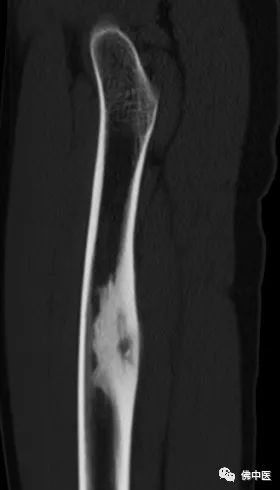

小陆病灶所在分布有重要的神经血管

经诊断,小陆同样患有骨样骨瘤。据其主治医生潘海文介绍,经影像学检查,病灶位于大腿中上段内后方,大腿内后方分布有重要的神经血管,加上瘤巢细小,直径仅约7毫米,术中探查犹如大海捞针。

小陆右腿检查片